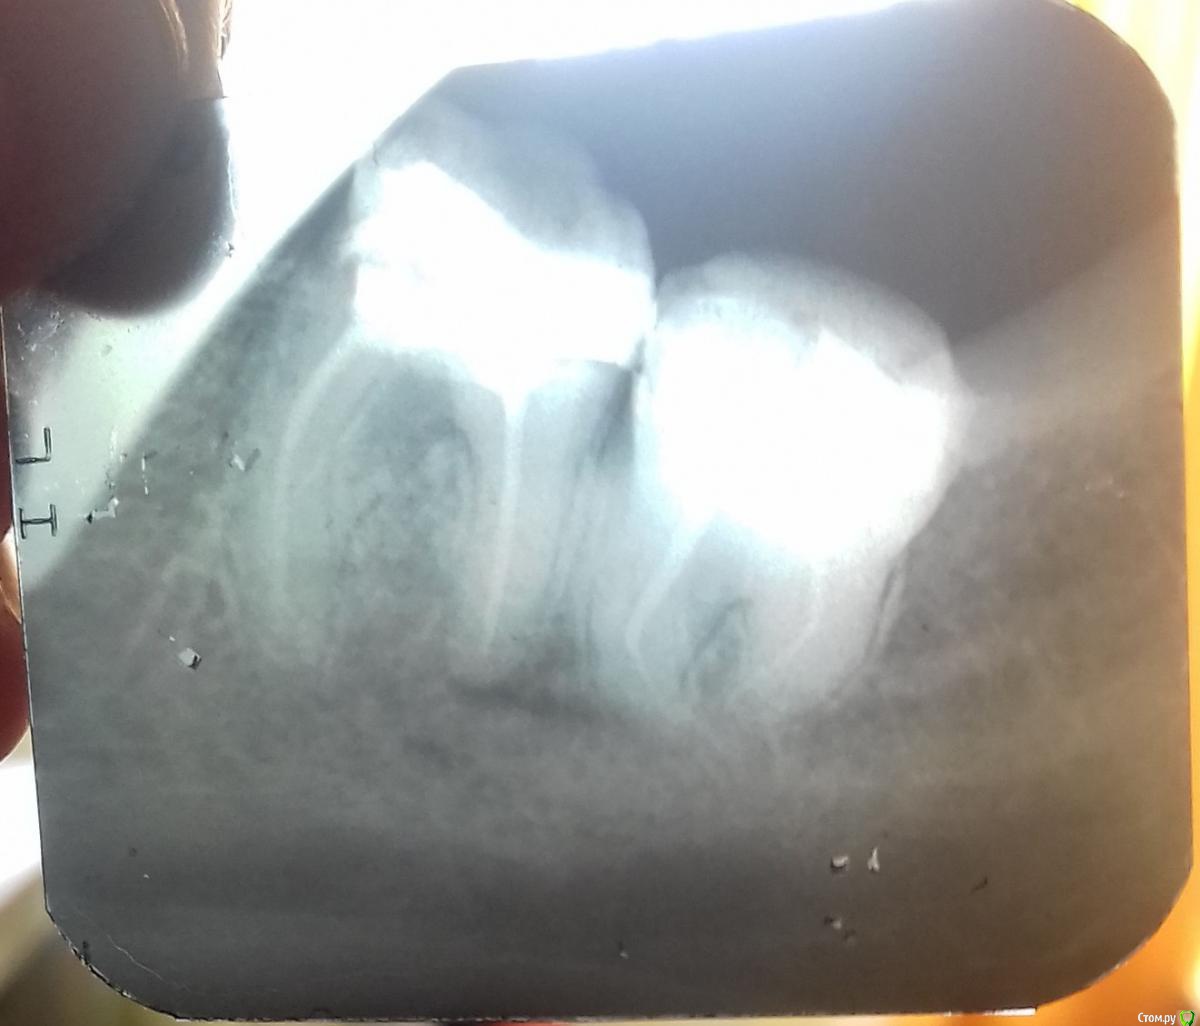

litvinenko1976 Опубликовано 29 января, 2017 Поделиться Опубликовано 29 января, 2017 Добрый день! Подскажите пожалуйста можно ли спасти зуб? В 37 зубе свищ. Первый раз образовался в 2010 году после лечения. Позже в 210 году был у другого врача был перелечен один канал, свищ почти прошел, не беспокоил. Примерно полтора гола назад образовался снова. Врач не перелечивает, говорит если будет беспокоить – удаление. Самый важный вопрос - Можно ли вылечить этот зуб? В 37 зубе свищ. Первый раз образовался в 2010 году после лечения. Позже в 210 году была у другого врача был перелечен один канал, свищ почти прошел, не беспокоил. Примерно полтора гола назад образовался снова. Врач не перелечивает, говорит если будет беспокоить – удаление. Самый важный вопрос - Можно ли вылечить этот зуб? Если да, то к какому врачу в Саратове можно обратиться? Ссылка на комментарий

Доктор Добрых Дел Опубликовано 29 января, 2017 Поделиться Опубликовано 29 января, 2017 Здравствуйте, дело не в каналах. Проблема в том, что есть воспаление между корнями. Причина скорее всего в трещине на дне полости (под пломбой). Либо перфорация. Перелечить и сохранить не удастся. Здесь показания к удалению и имплантации. 1 Ссылка на комментарий